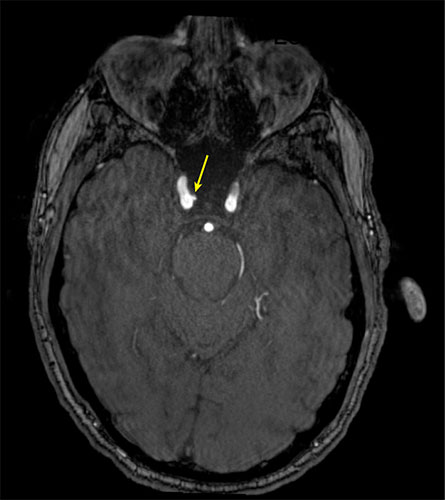

Representative axial time-of-flight MR angiography image shows a medially projecting intracranial aneurysm originating from the right cavernous segment of the internal carotid artery.

Representative axial time-of-flight MR angiography image in a 35-year-old male participant shows a medially projecting intracranial aneurysm (arrow) originating from the right cavernous segment of the internal carotid artery.